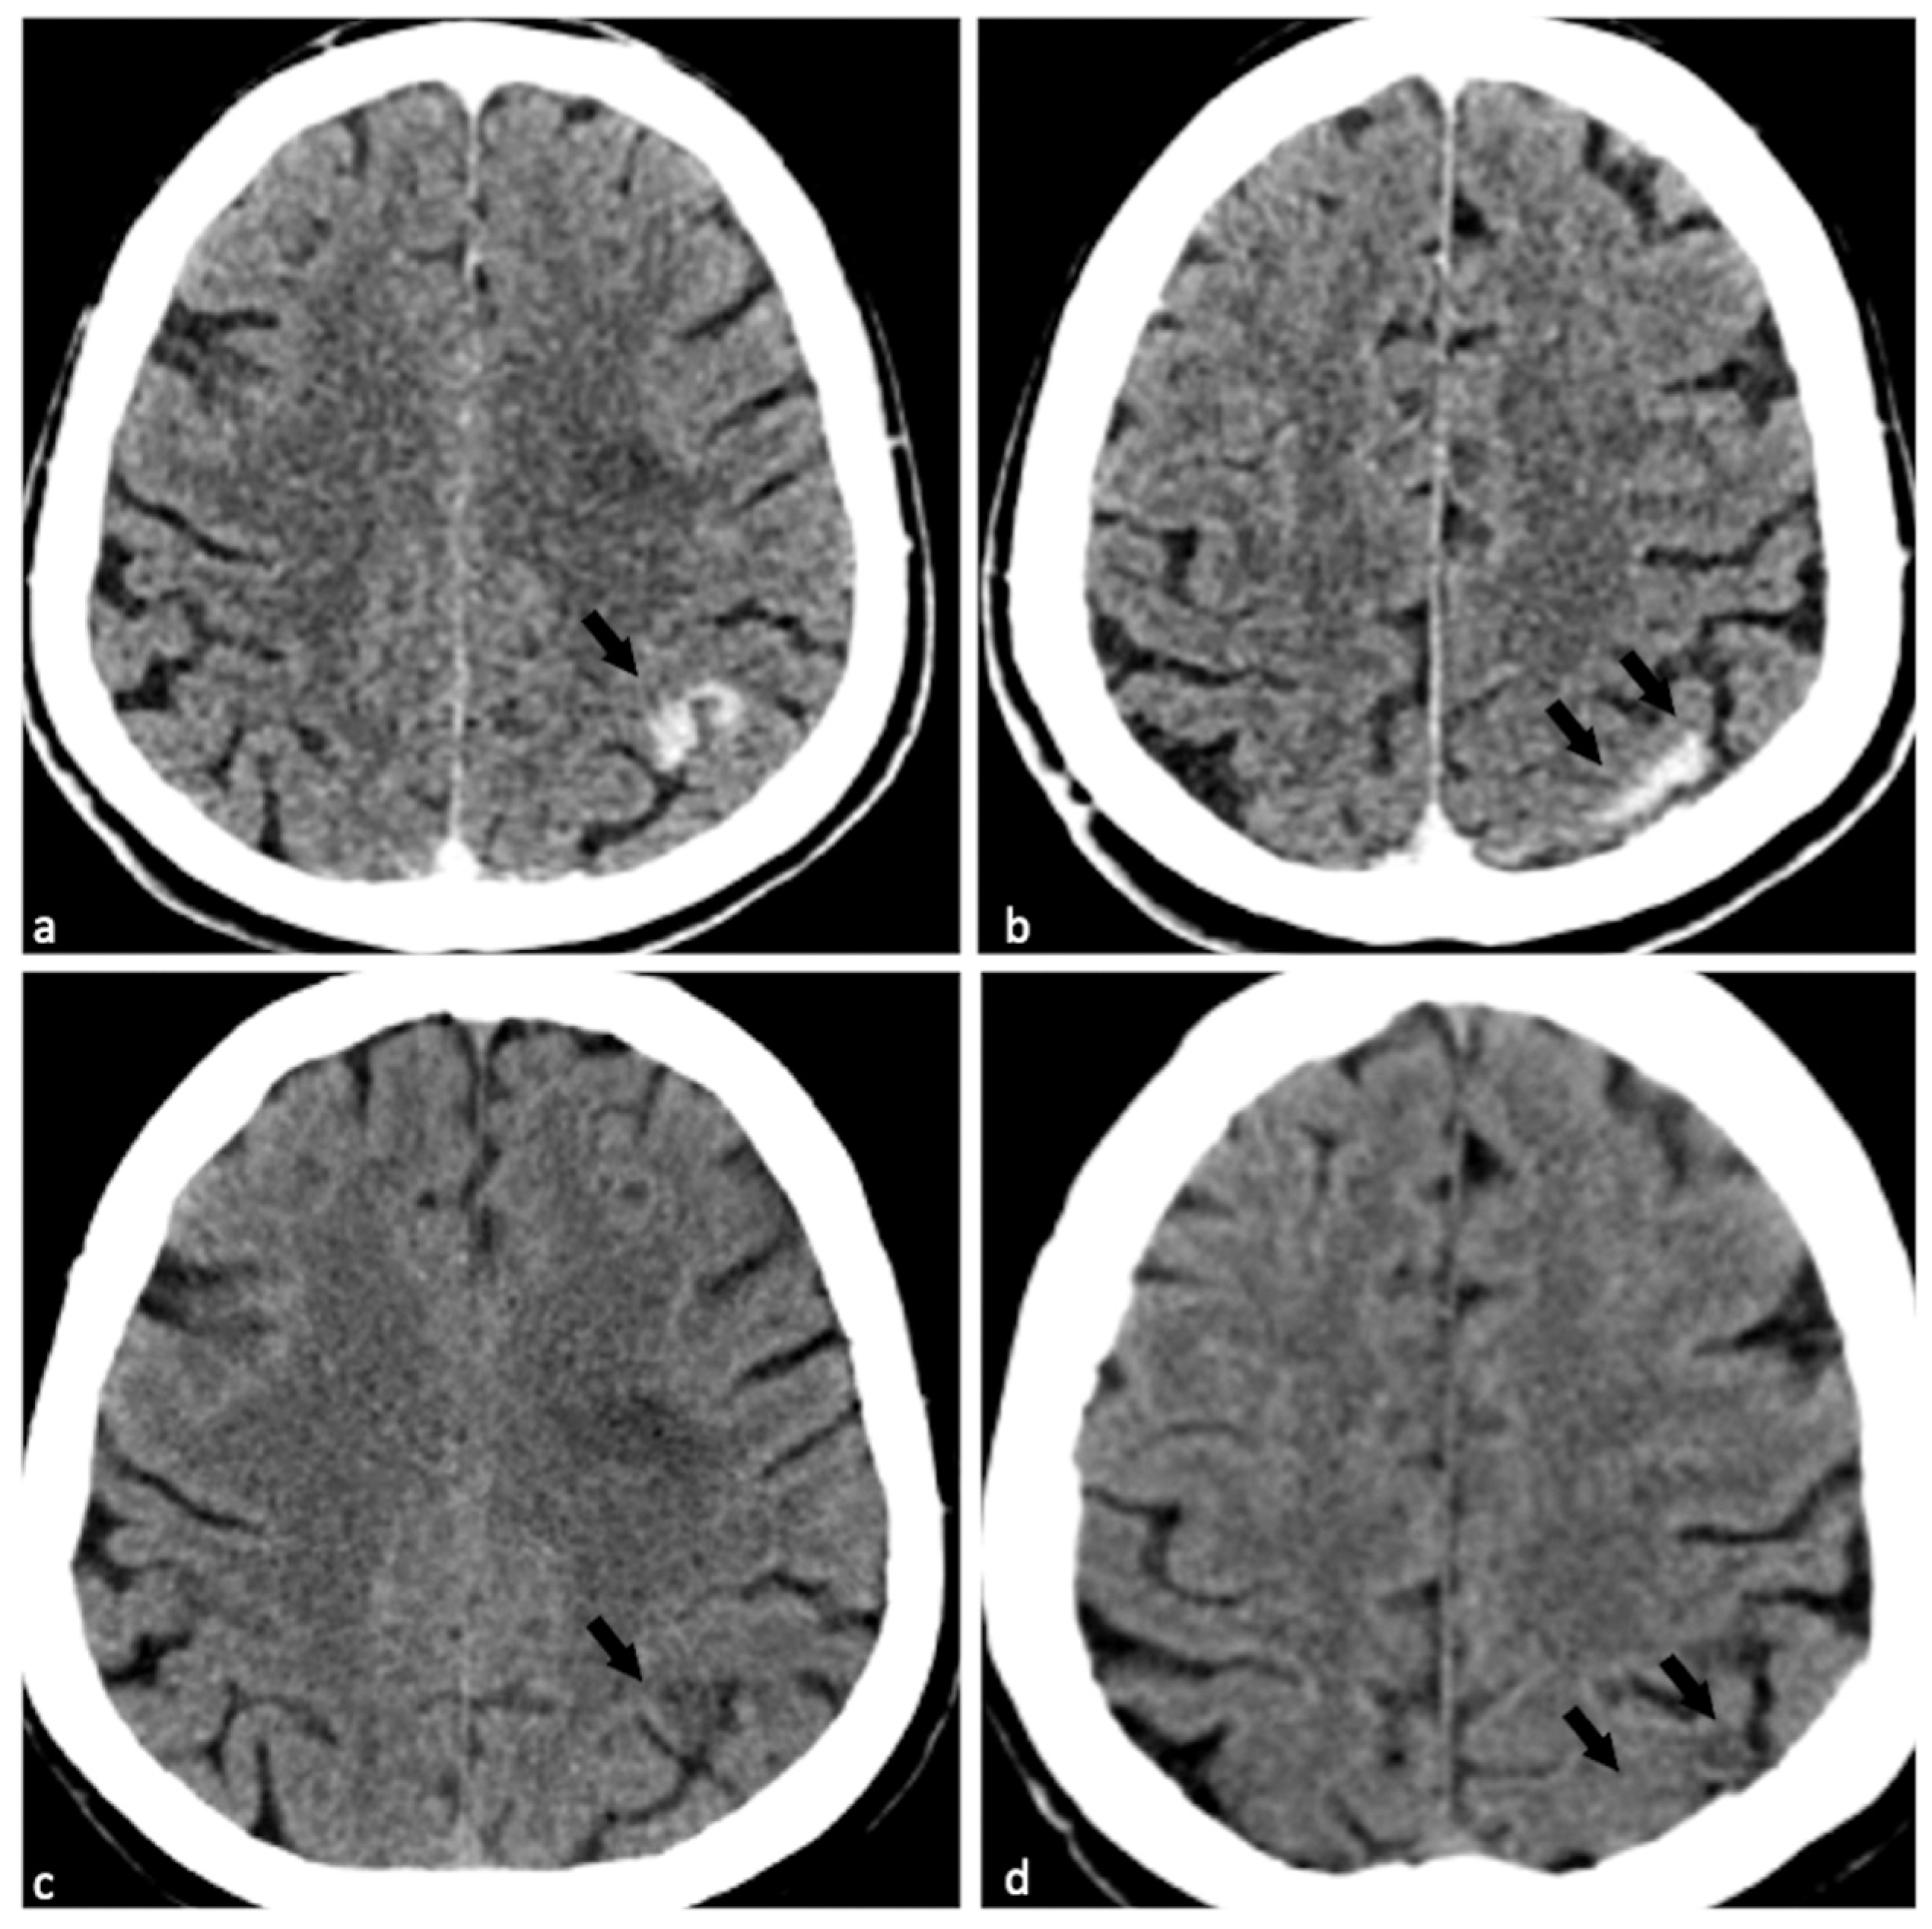

Dual-Energy Computed Tomography (DECT) for Diagnosing Contrast-Induced Encephalopathy (CIE) Mimicking Intracranial Hemorrhage (ICH): A Rare Case

Shen, Y.; Ye, T. Dual-Energy Computed Tomography (DECT) for Diagnosing Contrast-Induced Encephalopathy (CIE) Mimicking Intracranial Hemorrhage (ICH): A Rare Case. Diagnostics 2025, 15, 2426. https://doi.org/10.3390/diagnostics15192426